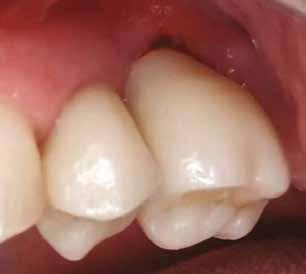

1. a–d. ábra: Műtét előtti állapot mind a négy páciensnél. 1. eset (a). 2. eset (b). 3. eset (c). 4. eset (d).

Az alábbi esettanulmányhoz négy pácienst választottunk ki (1. táblázat). Minden esetben egy, vagy több fog pótlására volt szükség, amelyhez kerámiaimplantátumokat használtunk. Valamennyi páciens általános egészségügyi állapota jó volt.

digitális implantátumtervezés követett (SICAT és Sidexis, mindkettő Dentsply Sirona; 1. ábra).